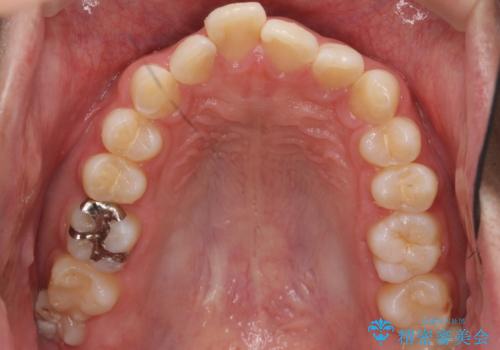

左のかみ合わせが1本分ずれていましたが、機能的には問題ないのでそのまま変えずに治療しています。

ずれている分を、上の歯を1本抜くか(ワイヤー矯正になります)、右上の奥歯を1本分後ろに送るか、そのまま前歯を並べるのかを選んでいただきました。

右のかみ合わせをそのままに、最小限の動かし方で見た目を改善しました。